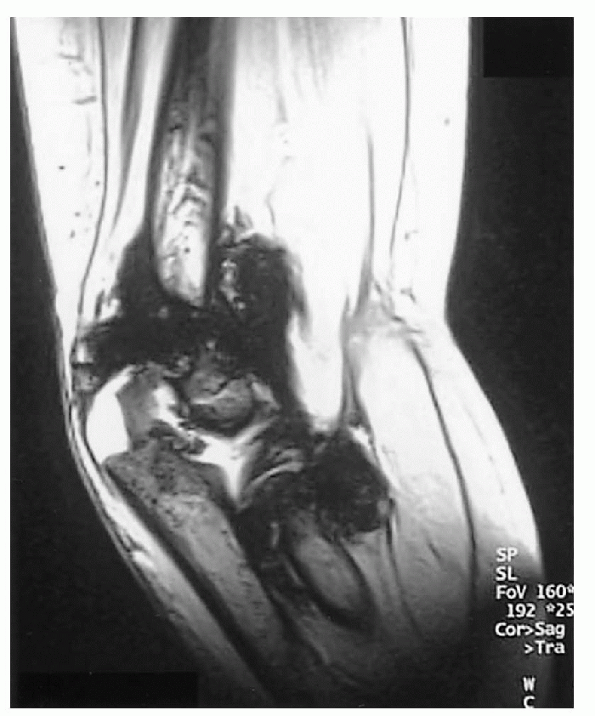

Hemosiderin deposits can be seen on MRI (Fig. 26.1-2), as can subchondral and intraosseous cysts or hemorrhage (Figs. 26.1-3 and 26.1-4).

Figure 26.1-2

Right elbow magnetic resonance image of a 6-year-old boy with hemophilia. Synovial hypertrophy and large hemosiderin deposit are seen. |

Figure 26.1-3 Left ankle sagittal magnetic resonance image of a 6-year-old boy with hemophilia. Subchondral bone cyst is seen.